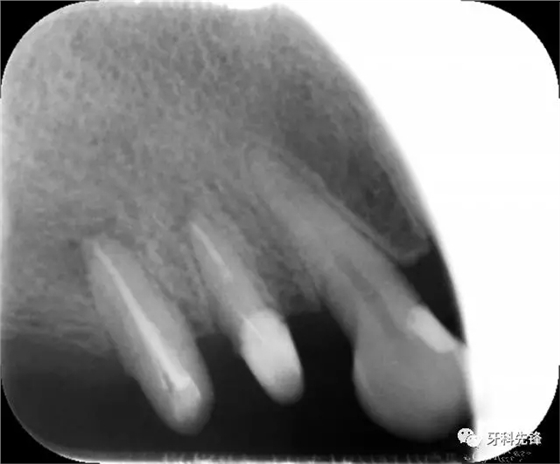

圖1術(shù)前X光片

X 示:15 根管透射,根尖有陰影

14根管阻射,恰填,無(wú)異常

46 根管阻射,恰填,根分叉骨密度降低,近中根尖陰影較大